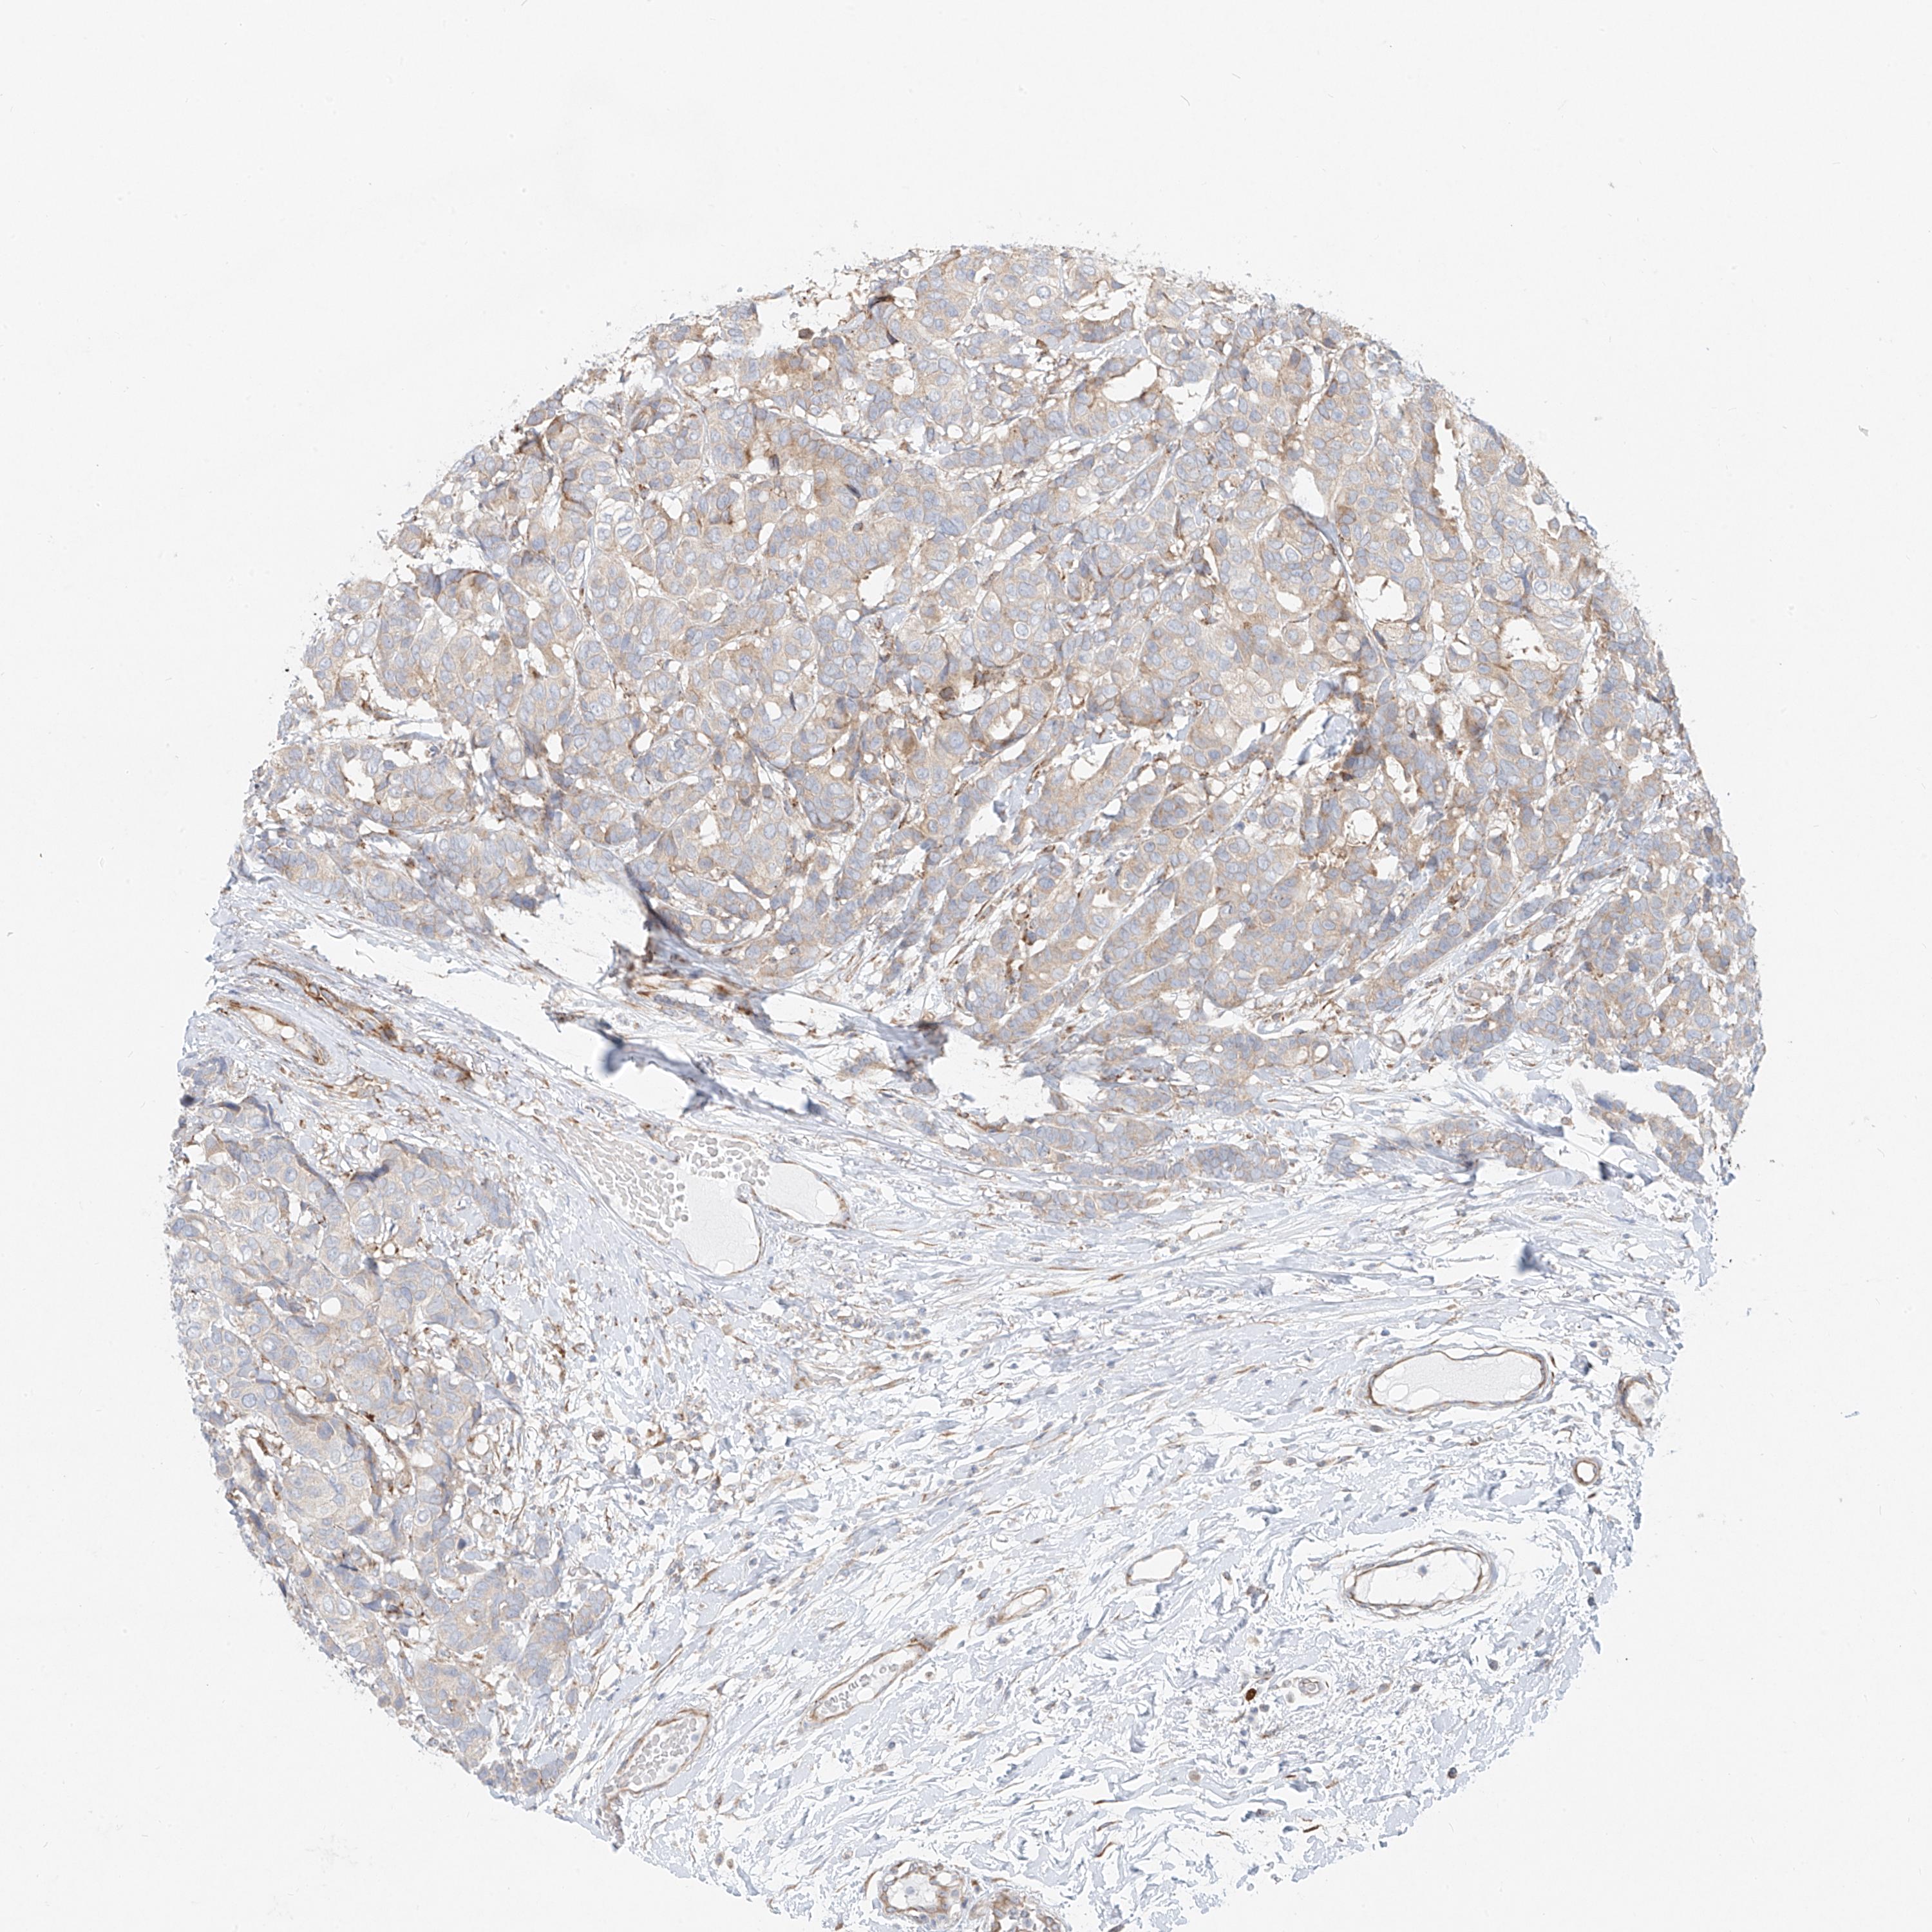

CANCER BREAST CANCER Show tissue menu

BRCA TCGA BRCA VALIDATION PROTEIN EXPRESSION